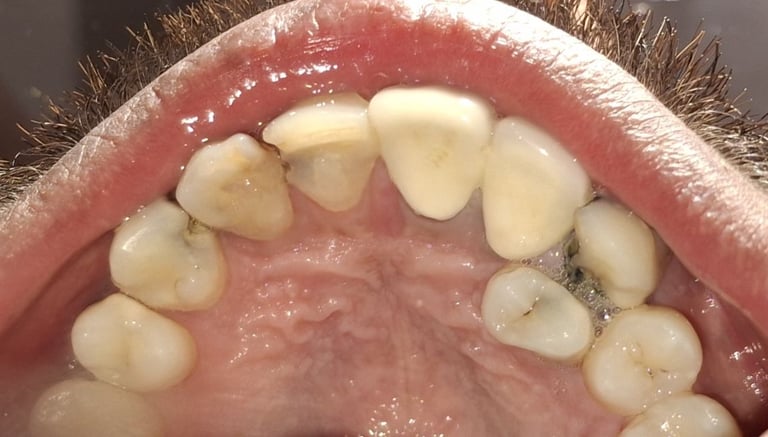

Tooth Colored Filling in Shyamal, Ahmedabad

Tooth-colored fillings are used to restore decayed or broken teeth while maintaining a natural appearance. These fillings blend seamlessly with your tooth color and help preserve your smile.

Before

After

All images shown here are real tooth colored filling cases treated at our clinic with patient consent.

At Shree Dental Care, cosmetic fillings are placed carefully with a focus on comfort, precision and long-term durability. We ensure minimal tooth cutting and natural-looking results.

If you are looking for aesthetic tooth colored filling in Shyamal, Ahmedabad, you can book an appointment with our clinic.